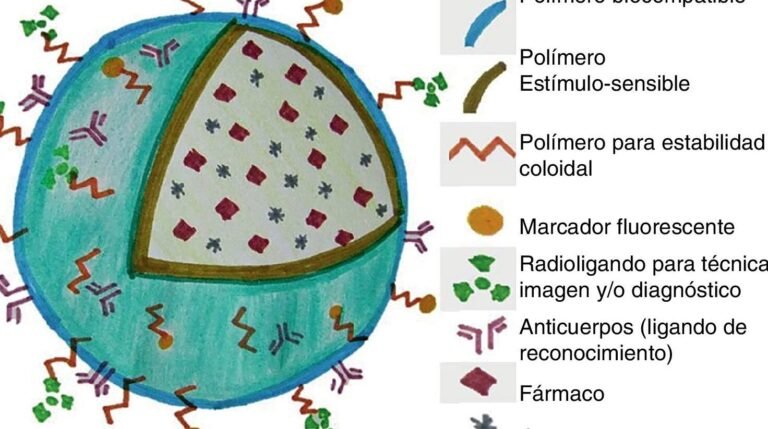

Los representan una innovación clave en el desarrollo de medicamentos más eficaces. Muchos compuestos terapéuticos presentan baja...

se ha convertido en un tema crítico en el campo de la nanotecnología y la medicina. Estas...

La representa un avance revolucionario en la medicina moderna, al integrar diagnóstico y tratamiento en un único...